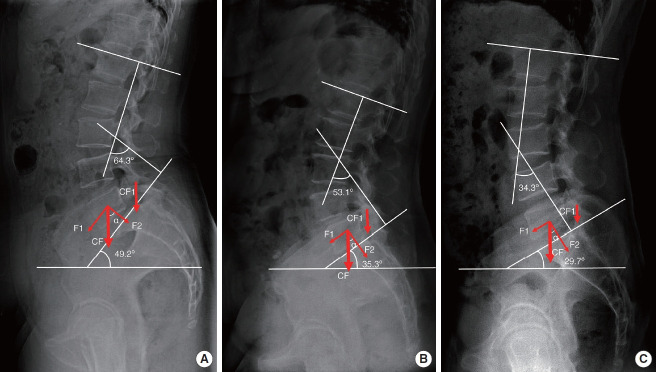

Results: Sacral slope (SS) and lumbar lordosis (LL) were the highest in the IS group, the second highest in the DS group, and the lowest in the NL group. Among the 3 groups, the L4 facet joint angle (FJA) was the largest in the IS group, the second largest in the NL group, and the smallest in the DS group. The L4 pedicle-facet joint angle (PFA) was the largest in the DS group, the second largest in the IS group, and the smallest in the NL group. Pearson correlation analysis showed that within each group, SS and LL were negatively correlated with FJA and positively correlated with PFA.